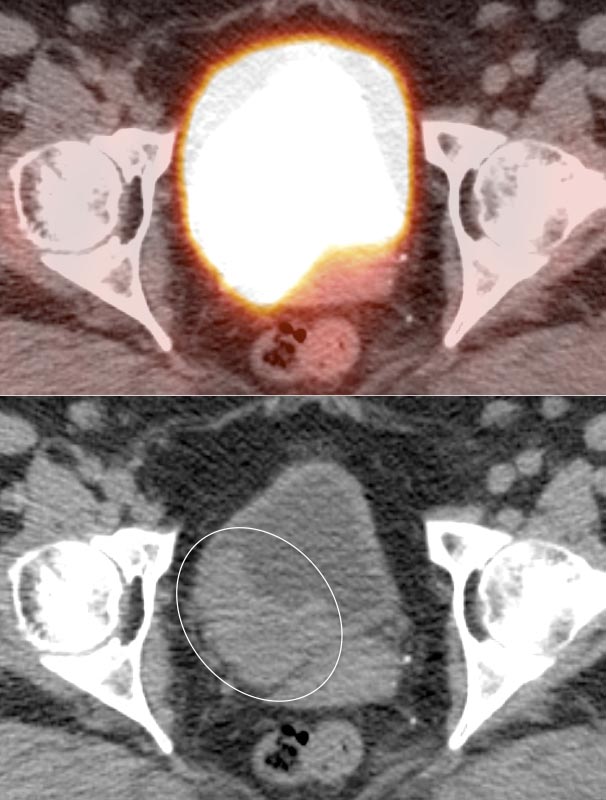

We do, however, recommend manual manipulation of image intensity of the bladder during interpretation (as is done when evaluating the brain) to try to differentiate hypermetabolic urine from a potentially FDG-avid bladder wall mass.